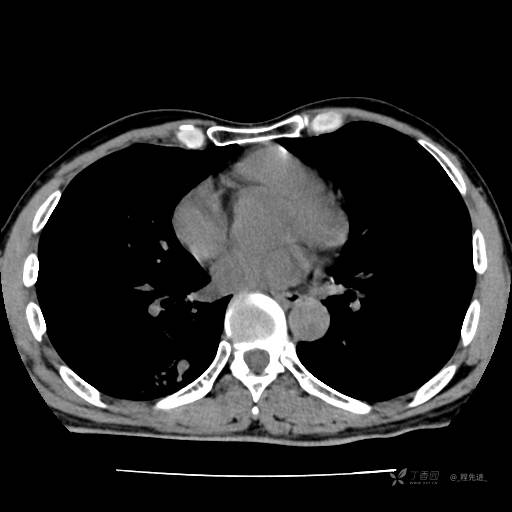

2月特别精彩病例|咳嗽、咳痰20余天,典型病例分享【结果已公布】

患者年龄:51岁

主诉:咳嗽、咳痰20余天

简要病史:20余天前开始出现咳嗽、咳痰症状,阵发性刺激性咳,白色粘痰,不易咳出,无发热,无咯血,无恶心、呕吐等不适,未诊治,咳嗽、咳痰症状持续存在。

体格检查:T:36.3 ℃ P:79 次/分 R:20 次/分 BP:128/64 mmHg,神志清楚,呼吸平稳,双肺呼吸音粗,右下肺闻及细湿性啰音。心率79次/分,节律整齐,各瓣膜听诊区未闻及病理性杂音。腹部未见异常,双下肢无水肿。

辅助检查:我院门诊胸部CT示:如下。心电图:窦性心律;正常心电图。